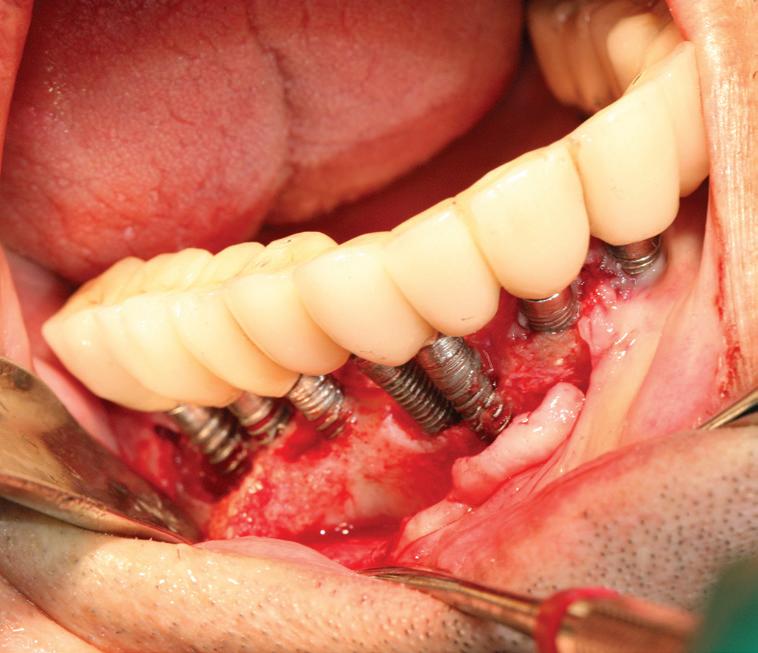

– 5 cavity classes